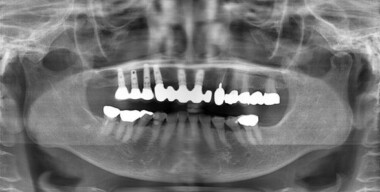

患者様からよく寄せられる質問の一つに、「インプラント治療って本当のところどうなの?」というものがあります。私がインプラント治療を始めたのが30歳の頃のことです。それから既に26年が経過しており、その間、名取歯科医院は数々の患者さんを治療してきました。その中で、36歳の時に担当させていただいた患者さんがいらっしゃいます。

治療後20年が経ち、患者様は80歳となりましたが、ぴんぴんとしたお元気ぶりに驚かされます。

患者さんは検診の度に「入れ歯にしなくて良かった」とおっしゃり、お身体も健康そのもの。これからも特に問題なく経過していくものと期待されます。この喜びに満ちた結末は、インプラント治療の功績であることは間違いありません。患者さんが80歳にして自身の歯でしっかりと食事を楽しんでいらっしゃる姿は、治療の成功を象徴しています。